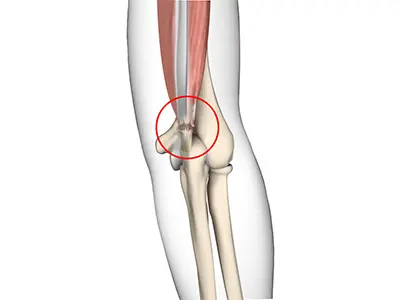

Triceps Injuries

The triceps or triceps brachii is a crucial muscle of the upper arm (humerus). It runs along the upper arm bone between the shoulder and elbow.

Triceps Tendonitis

Triceps tendonitis is inflammation of the triceps tendon, the tissue that connects the triceps muscle on the back of the upper arm to the back of the elbow joint